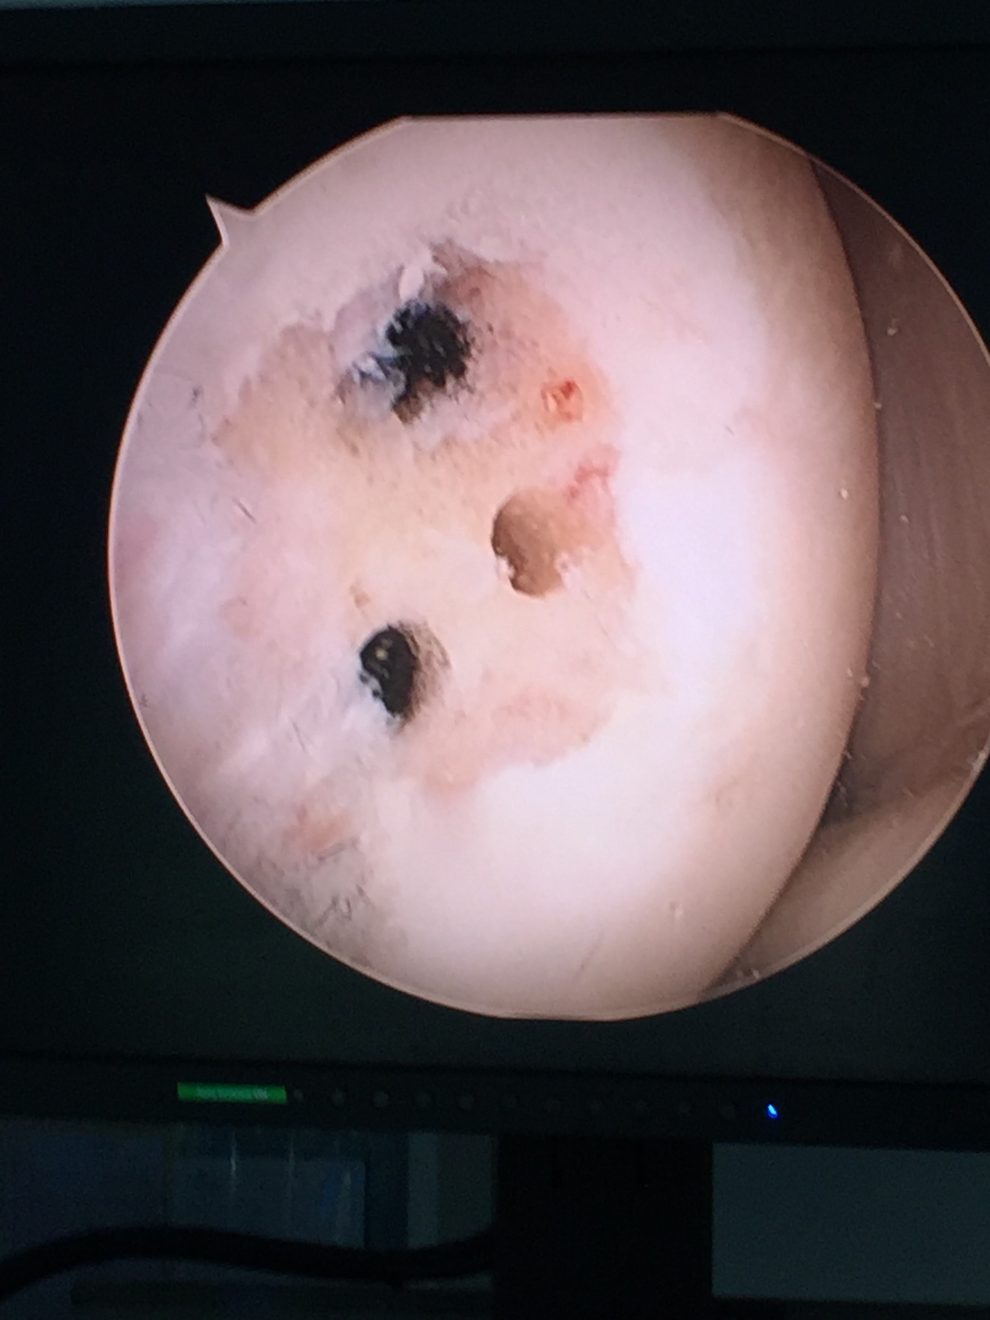

- wykonać zabieg artroskopii stawu. Możemy poddać leczeniu praktycznie wszystkie elementy stawu kolanowego, naprawiając łąkotkę, stymulować chrząstkę do naprawy, rekonstruować więzadła. Choć chrząstka szklista w stawie nie regeneruje się do nowej chrząstki, poprzez wykonanie zabiegów naprawczych, które polegają na oczyszczeniu uszkodzonej powierzchni chrzęstnej, a następnie wykonaniu mikrozłamań, nawierceń lub implantacji specjalnych węglowych pinów, aktywizujemy komórki szpiku (komórki mezenchymalne), które mają bardzo duży potencjał biologiczny. Pokrywają one uszkodzoną powierzchnię chrzęstną i wypełniają ubytek tkanką chrzęstną włóknistą, która nie jest chrząstką szklistą, ale bardzo ją przypomina. Zabieg ten uwalnia pacjenta od bólu i poprawia jakość jego życia.

Obrazy z artroskopii stawu